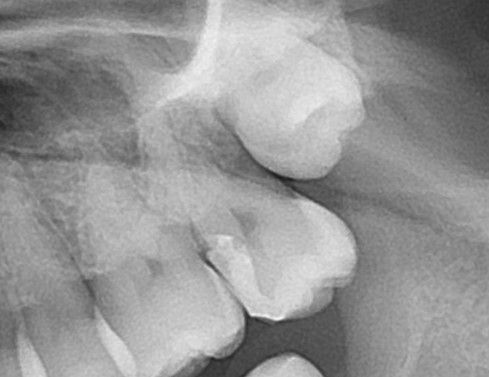

エックス線(レントゲン検査)で歯の中を見てみましょう。

一番奥に生えてきていない親知らずがあります。一つ手前の白く詰め物がされている歯です。

☝歯の神経は赤く記したここにあり、

☝青い箇所がレジンが詰めてあります。

神経に近く、ほぼ神経に触れるように詰め物がされています。

☝詰め物がうまく詰められておらず、飛び出て段差になっていることも見て取れます。